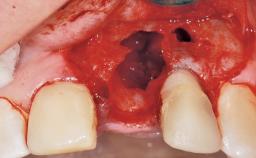

Late Flapless Placement of an Implant in a Maxillary Left Central Incisor Site

A 39-year-old male patient presented with a chief complaint of discomfort and gingival discoloration around his maxillary left central incisor. He was in good general health and was a non-smoker. His past dental history was significant because of the traumatic fracture of tooth 21 in a sporting accident at age 13. Initial dental treatment included endodontic therapy and a full-coverage restoration. The patient became symptomatic 5 years later, when structural failure of the tooth resulted in the dislodgment of the crown. Endodontic retreatment, apical surgery, and post-and-core restoration were performed.

| Bone Augmentation | Horizontal|Staged |

| Augmentation Materials | Xenogenous|Membrane |